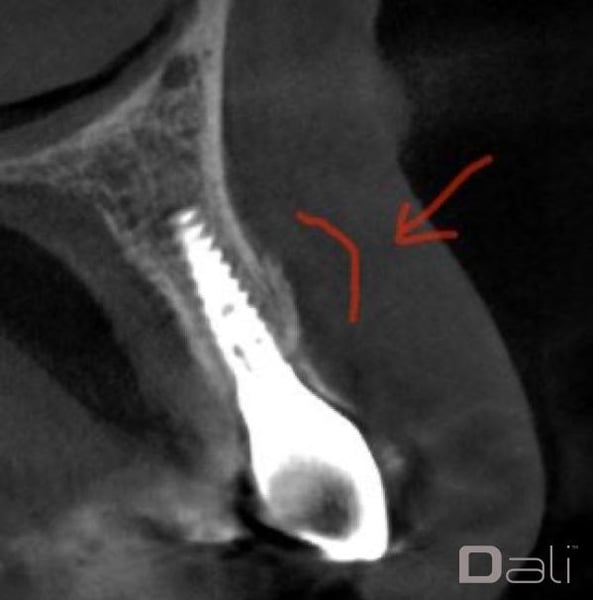

A palatal full thickness flap confirmed our suspicion. The root fragment was removed, the defect was degranulated, and the implant surface was decontaminated with a Nd:Yag laser.